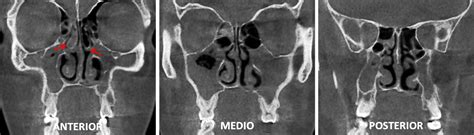

A la hora de realizar el diagnóstico, se debe realizar una exploración de las manifestaciones clínicas y radiológicas que presenta el paciente. A nivel radiológico, observamos un engrosamiento de la capa mucosa que tapiza los senos maxilares, posibles anomalías anatómicas, pólipos nasales etc. La tomografía axial computerizada, también conocida como TAC, es una imagen radiológica que da muchos detalles de los pólipos una vez se ha determinado su existencia.